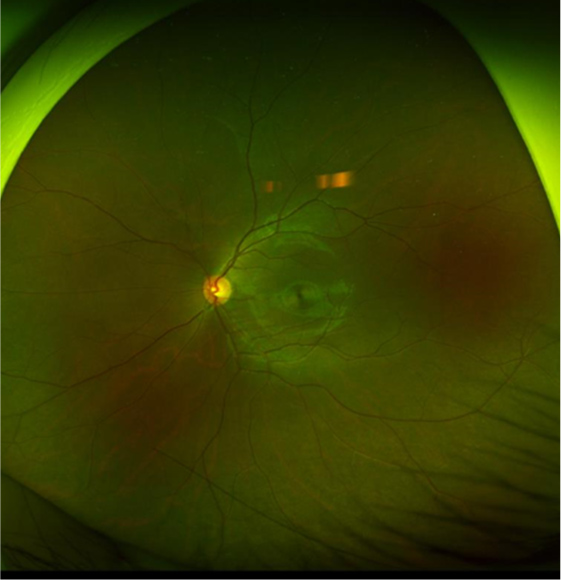

眼底写真検査

網膜の中心部(黄斑・視神経付近)の写真を撮影し、網膜疾患や血管異常の有無を確認

広角眼底写真撮影(最周辺部)

網膜の周辺部まで広範囲を撮影し、網膜裂孔や変性などの異常を中心部以外も含めて早期発見

自発蛍光眼底写真

網膜に含まれる自発蛍光物質を撮影し、加齢黄斑変性・網膜萎縮など、網膜組織の機能異常や変化を評価